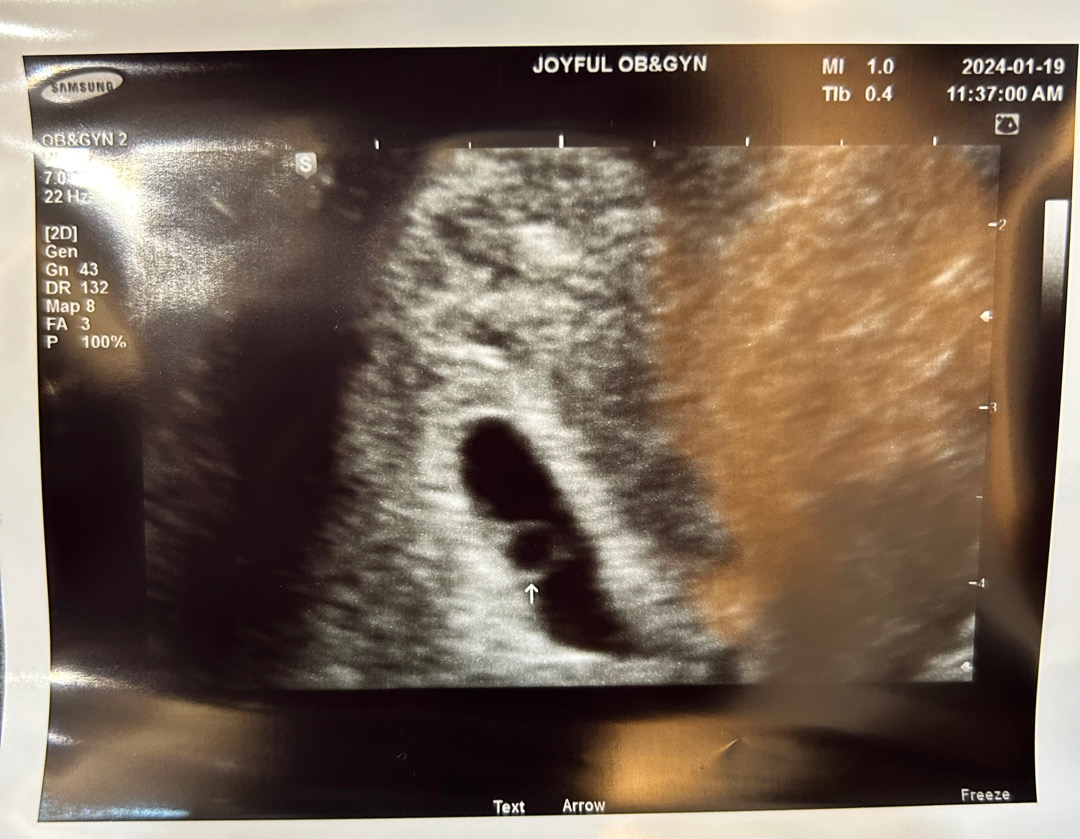

처음 본 건 1/15(월) 네이버 기준 4주 2일차에 아주 작은 아기집만 봤구요 오늘은 질염 증상때문에 갔다가 초음파 다시 봤어요 아기집이 커졌고 난황도 보였답니다!!🥰 (오늘-4주6일) 원래 2주 뒤 가서 산전검사 하려고 했는데 오늘 하고 왔어요 제가 몇 년 전에 갑상성항진증이 있었어서 검사 땡겨서 하자 하시더라구요 ㅎㅎ 그래서 보건소 안 가고 병원에서 한방에 하고 왔슴다!!